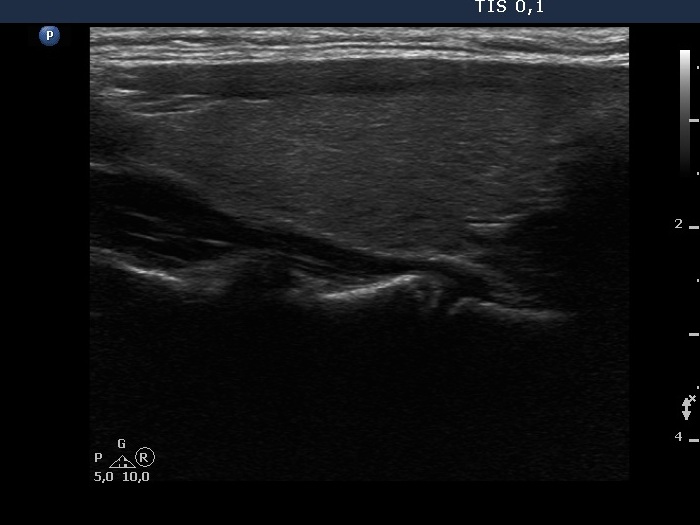

The shape of the nodule - case 718 (ultrasonographic picture 8)

Left lobe, longitudinal scan.